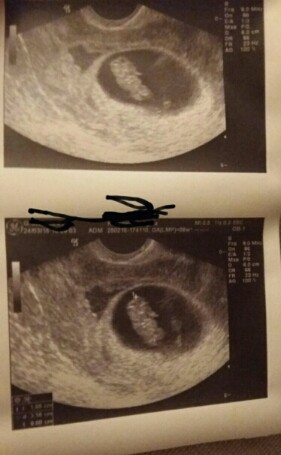

Ha naumialam się w końcu :) chwałę się :P musiałam tylko przyciąć obraz bo rozmiar był za duzy

Princeseczka slucznie!! To po lewej to krwiak?

Princeska cudny dzidziol:):):)